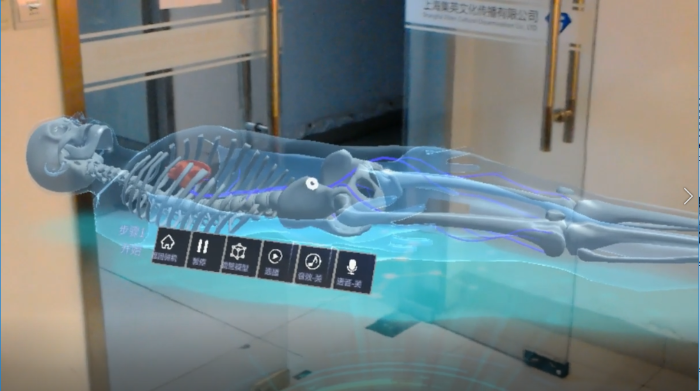

左心耳封堵術流程展示(Watchman)

模擬穿刺、造影、放置等步驟

心臟、血栓房顫展示

HoloLens項目體驗:

HoloLens醫療項目截圖: